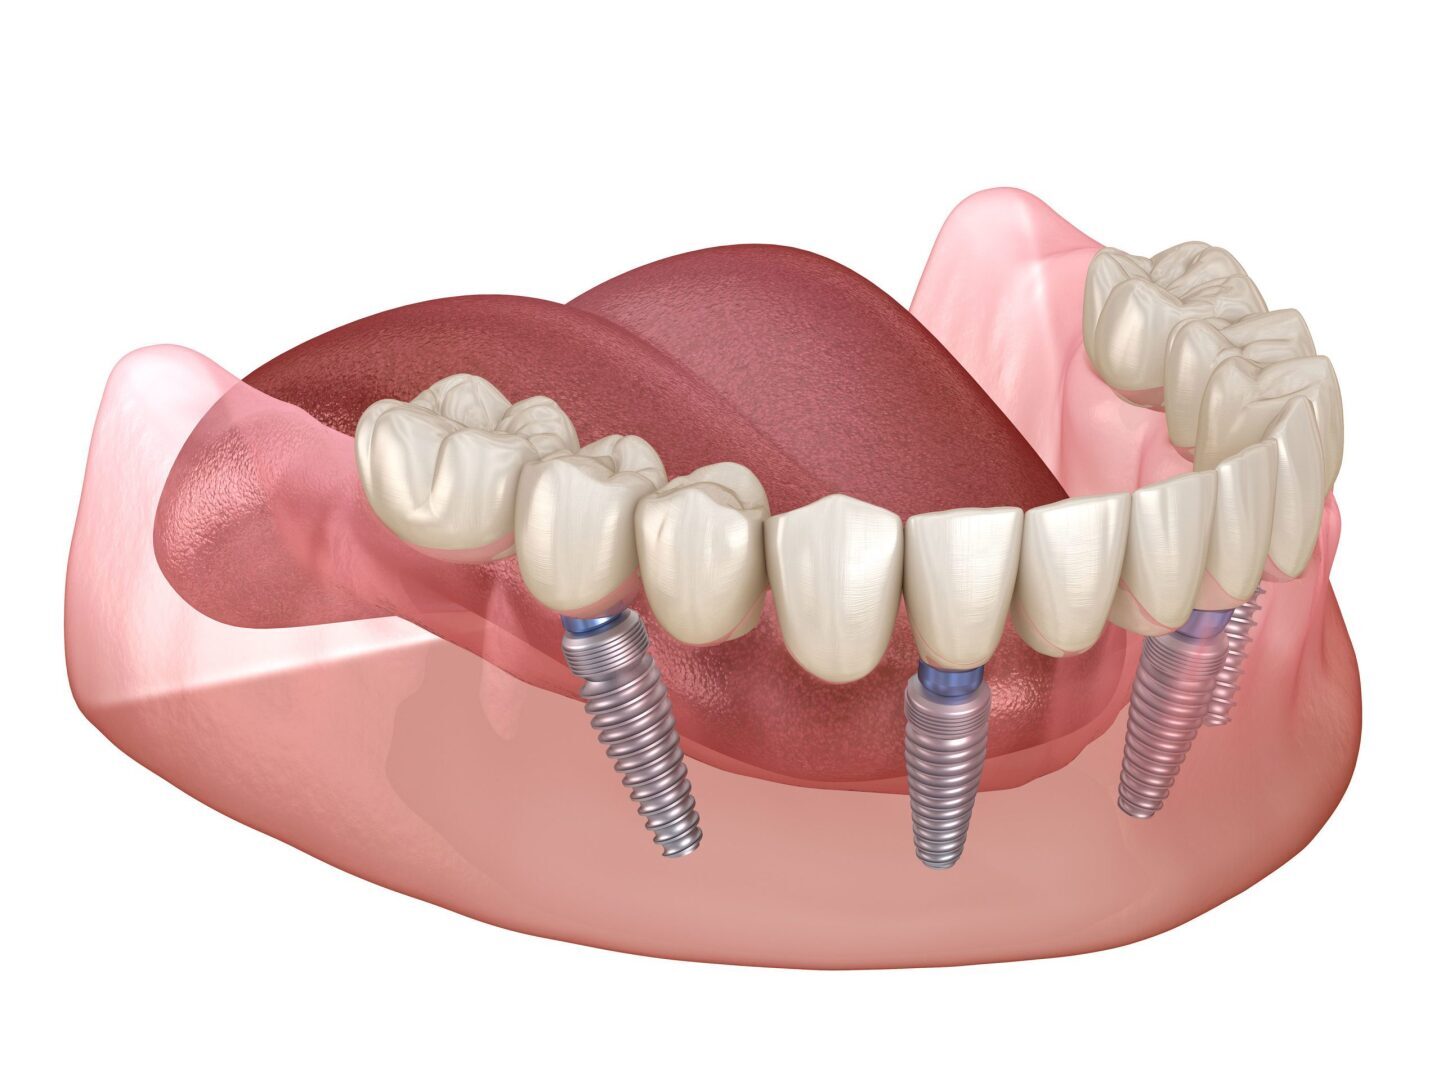

Чем мотивируют, кость тонкая.

заметьте, делают все наискосок. До Рязанских профессоров и лоботрясов это не доходит

Москва хоть и ездит в Рязань зубы лечить из-за цен, но у них другое, пломбу поставить или один имплантат